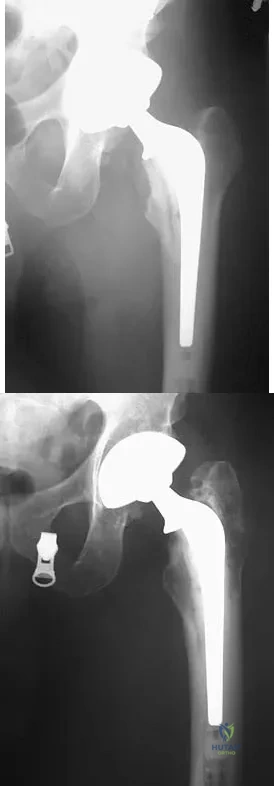

Figures 4a and 4b show the radiographs of a 32-year-old man who has right groin pain with activity or prolonged standing. Which of the following factors would not prohibit consideration of acetabular liner exchange and grafting of the defects?

Explanation

A patient who underwent primary total hip arthroplasty 7 years ago that resulted in excellent pain relief and a normal gait now reports pain and a limp. Postoperative and current AP radiographs are shown in Figures 2a and 2b. What is the most likely cause of the pathology seen?

Explanation